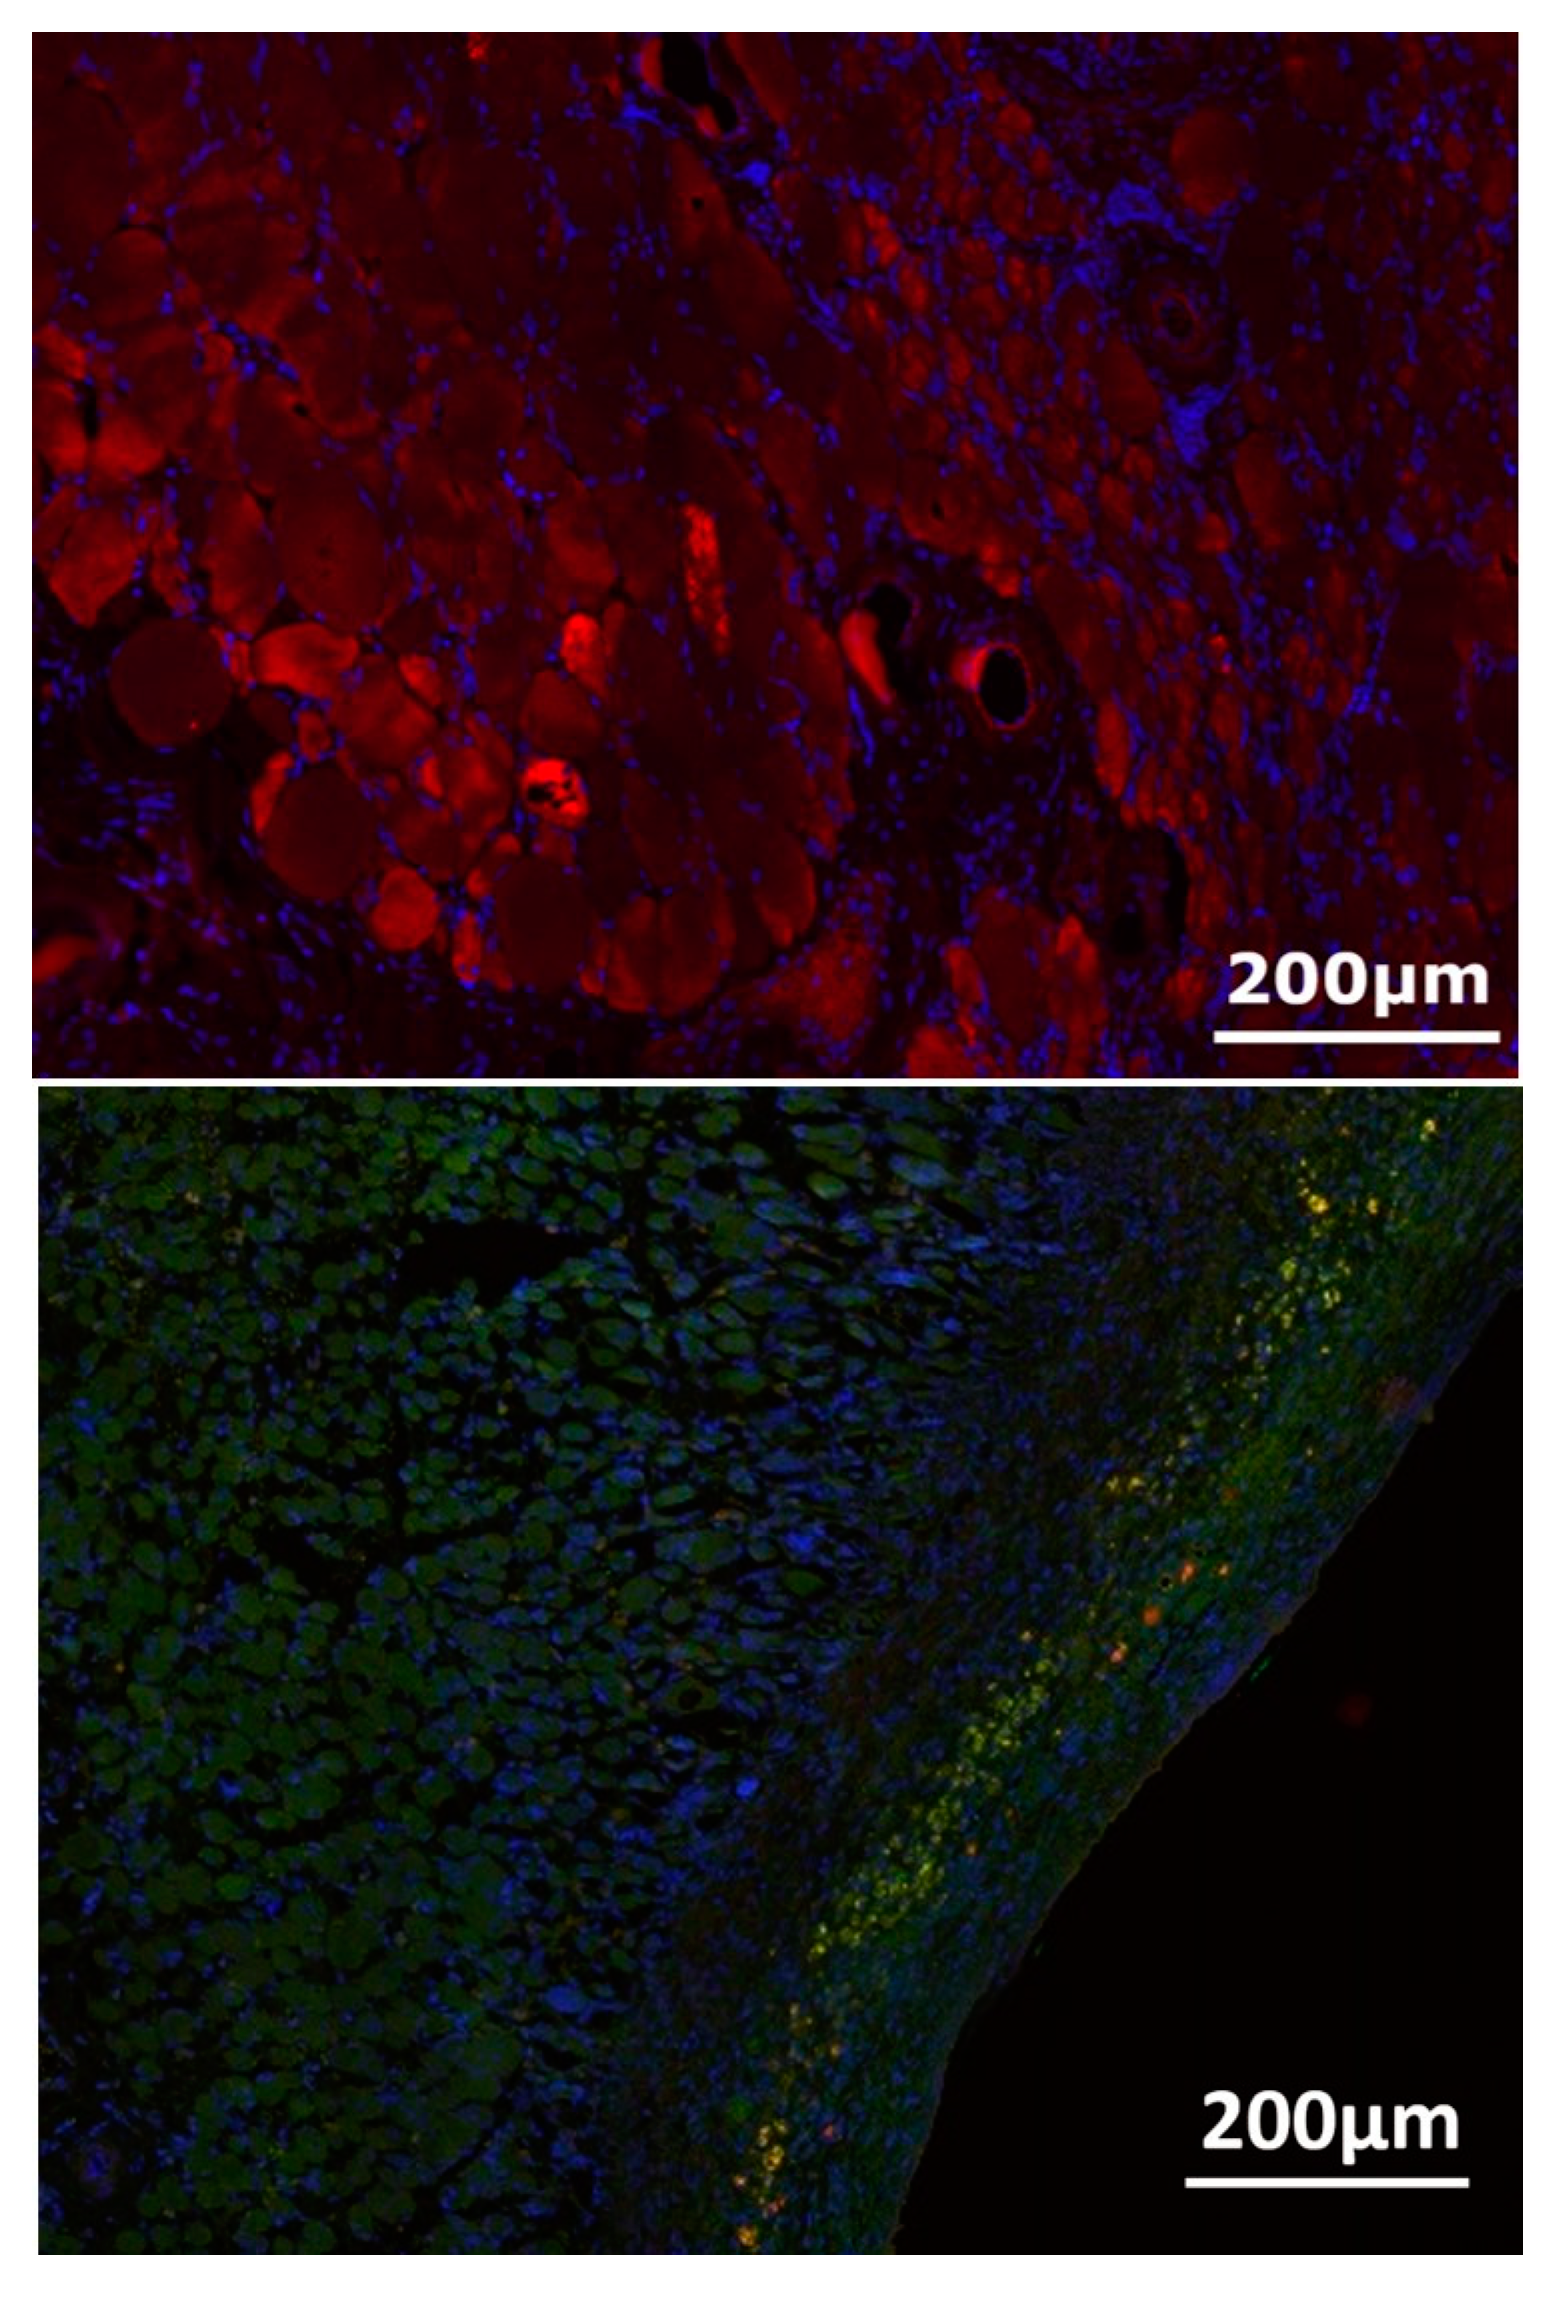

3.4. Nerve-Muscle-Junction and Myogenic Marker Expression

3.5. Myofiber Morphology and Macrophage Invasion

| Vessel Radius (µm) | Number of Vessel Lumen |

|---|---|

| 0.1–20 | 165.8 ± 109.5 |

| 20.1–40 | 17.4 ± 2.7 |

| 40.1–60 | 3.4 ± 1.5 |

| 60.1–80 | 1.8 ± 1.6 |

| 80.1–100 | 1.4 ± 0.9 |

| 100.1–120 | 0.4 ± 0.5 |

| 120.1–140 | 0.2 ± 0.4 |

| 140.1–160 | 0.2 ± 0.4 |

| 180.1–200 | 0.4 ± 0.5 |

| 220.1–240 | 0.4 ± 0.9 |

| 240.1–260 | 0.2 ± 0.4 |